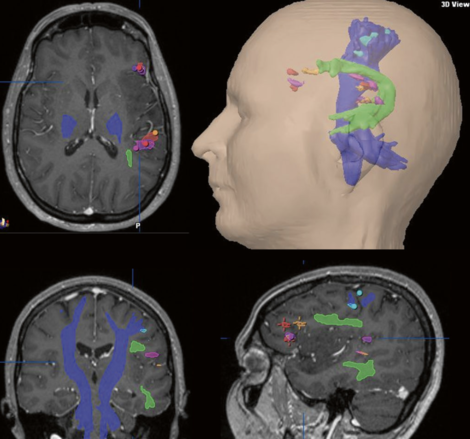

Proton bevæger sig med Brownske bevægelser primært i extracellulært rummet. I en given lille voxel kan protonbevægelsen være helt tilfældig (isotrop) eller i en speciel retning på grund af begrænsning af dens bevægelsesfrihed (anisotrop) som i myeliniserede axoner.

For at retningsbestemme skal DTI undersøgelsen foregå i mindst 6 forskellige retning, derefter anvendes 3D Gaussisk sandsynlighedsberegning til bestemmelse af 3x3 matriks som kaldes en diffusion tensor. En diffusion tensor er karakteriseret ved en eigen value og en eigen vector og kan man matematisk bestemme retningen af bevægelse. FA (fractional anisotropi) angiver graden af anisotropi med en FA-værdi på 0 sv.t. komplet isotopi = helt tilfældig bevægelse, til FA=1 sv.t. komplet anisotropi med udelukkende bevægelse i en retning. I en visuel fremstilling af retning vil en FA-værdig på = svarer til en kugle (en cirkel i planet) mens en FA-værdi på 1 vil svarer til en linje. FA=1 findes ikke i biologisk væv og de vil i stedet have ellipse form.

DTT fremstilles ved at tegner baner gennem eigen vektors i tilstødende voxels, man sætter typisk grænser for skarpt en "tract" mål dreje og minimums længde af de baner der skal findes.